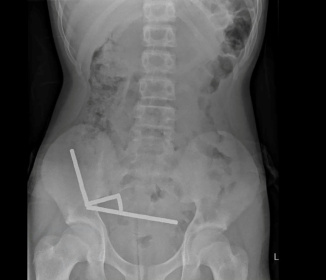

This undated handout released on October 24, 2025 from the New Zealand Medical Journal (NZMJ) shows an x-ray image of pieces of high-power magnets clumped up in the intestines of a New Zealand teenager in Tauranga - Handout (AFP)

Wellington (AFP) - A 13-year-old boy in New Zealand swallowed up to 100 high-power magnets he bought on Temu, forcing surgeons to remove tissue from his intestines, doctors said on Friday.